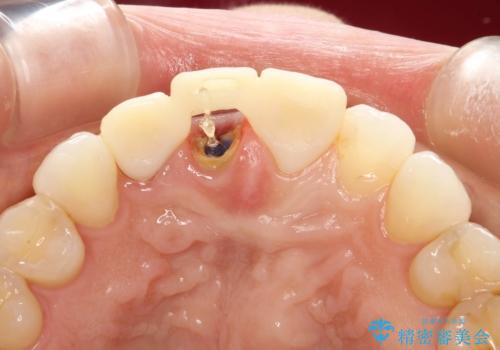

- 子どものときにワイヤー矯正をしていたが、後戻りによって前歯のガタツキが気になってきたとのことで来院されました。

アライナー矯正希望だったため、インビザラインによる治療を行いました。